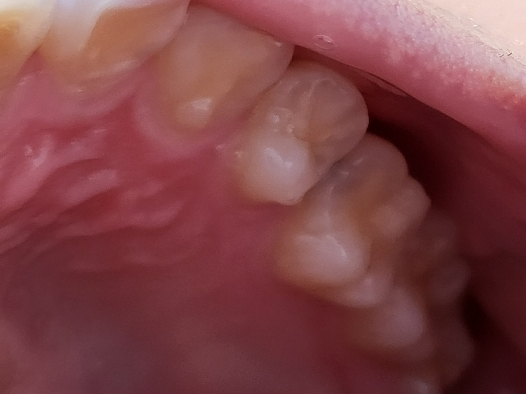

26번치아 치료 문의드립니다 검은색

26번치아 쪽에 검게 피인지 충치인지 모르는게

갑자기 생겨있네요..

사진으로 보았을 때는 보이는 부분 밑으로 충치가 있어 비춰보이는 것으로 보입니다. 부위 자체가 인접면이기 때문에 2급 수복을 해야 하며 경우에 따라서는 신경치료 이후 인레이를 해야할 수도 있습니다. 또한 사진으로 명확히 판단하기 어려우나 25번 치아 역시 충치가 있을 가능성을 염두해두고 치료 계획을 가지시는 것이 맞아보입니다.

색상으로 보면 치아 사이에 충치가 생긴것같습니다. 치과에 가셔서 먼저 검진을 받아보시고 치료를 받으시는게 좋을것같습니다. 인레이라는 치료를 하셔야될것같습니다.